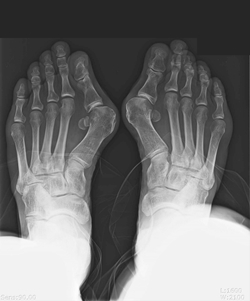

Çѱ¹ ¿©¼º 30~40%°¡ ¾Î´Â ¡®¹«Áö¿Ü¹ÝÁõ¡¯Àº ¾öÁö¹ß°¡¶ôÀÌ µÎ ¹øÂ° ¹ß°¡¶ô ÂÊÀ¸·Î ÈÖ´Â ÁúȯÀ¸·Î, ³²¼ºº¸´Ù´Â ¿©¼ºµé¿¡°Ô 5~6¹è ¹ßº´·üÀÌ ³ôÀº ÁúȯÀÌ´Ù. º¼ÀÌ Á¼Àº ±¸µÎ¸¦ ¸¹ÀÌ Âø¿ëÇÏ´Â °æ¿ì°¡ ³²¼ºµé¿¡ ºñÇØ »ó´ëÀûÀ¸·Î ¸¹±â ¶§¹®ÀÌ´Ù. ÇÏÁö¸¸ ¸¹Àº ¿©¼º¿¡°Ô ÈçÈ÷ ³ªÅ¸³¯ ¼ö ÀÖ´Â ÁúȯÀÓ¿¡µµ ºÒ±¸ÇÏ°í ¸ø»ý±ä ¹ßÀ» Å¿Çϸç ÅëÁõÀ» Âü°í Ä¡·áÇÏÁö ¾Ê¾Æ º´À» Ű¿ì´Â °æ¿ì°¡ ¸¹´Ù.

¹«Áö¿Ü¹ÝÁõÀÇ Áõ»óÀº »À°¡ ±ÁÀ¸¸é¼­ ¾öÁö ¹ß°¡¶ô ¾ÈÂÊÀÌ µ¹ÃâµÇ°í »öÀÌ »¡°²°Ô º¯Çϸç ÅëÁõÀ» µ¿¹ÝÇÑ´Ù. ÅëÁõÀÌ Áö¼ÓÀûÀ¸·Î ¾öÁö¹ß°¡¶ô ¾ÈÂÊ¿¡ ´À²¸Áö°Ô µÇ¸é ¹«ÀǽÄÀûÀ¸·Î ¾öÁö¹ß°¡¶ôÀ» µóÁö ¾Ê°í °È°Ô µÇ¾î ¹Ù´Ú¿¡ ±»Àº»ìÀÌ »ý±â°í ½Å°æÀÌ ¹¶ÃÄ ¹ß¹Ù´Ú ¾ÕÂÊ ºÎÀ§¿¡ ½ÉÇÑ ÅëÁõÀ» À¯¹ßÇÑ´Ù. ÅëÁõÀÌ »ç¶óÁö´õ¶óµµ ¾öÁö¹ß°¡¶ôÀÇ º¯ÇüÀº °è¼Ó ÁøÇØµÇ¾î ½ÉÇÒ °æ¿ì ¾öÁö ¹ß°¡¶ôÀÇ °üÀý¿°À¸·Î±îÁö ¹ßÀüÇÒ ¼ö ÀÖ´Ù. ¹«Áö¿Ü¹ÝÁõÀº ¿À·£ ½Ã°£ ¹æÄ¡ÇÒ °æ¿ì ¹«¸­°ú ôÃß±îÁö 2Â÷ÀûÀ¸·Î ÁÁÁö ¾ÊÀº ¿µÇâÀ» ÁÙ ¼ö ÀÖ¾î °¢º°ÇÑ ÁÖÀǰ¡ ÇÊ¿äÇÏ´Ù.